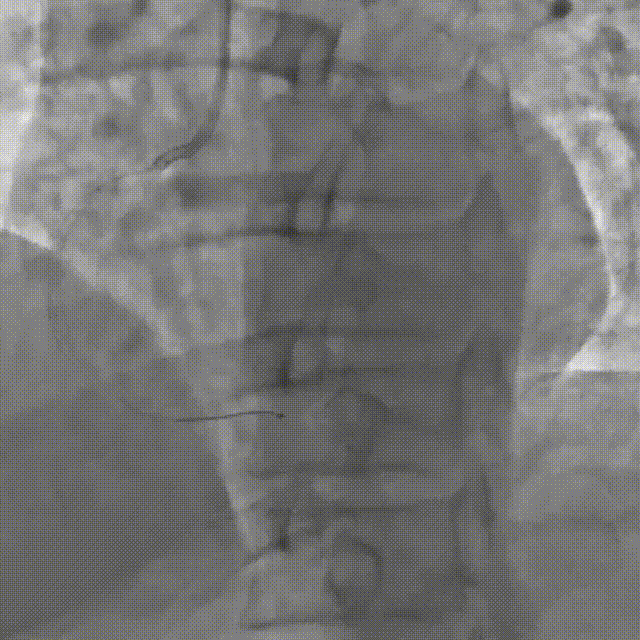

Corsair135辅助下先后尝试使用P200/G3导丝未能突破近端纤维帽,最终CP12突破后进入血管结构内,同时进行多角度确认。

尝试调整导丝重回真腔未成功,直接使用XTA导丝knuckle。

跟进corsair并交换LP球囊后,先后尝试G3/CP12/8-20等导丝穿刺均失败。

直接尝试逆向,RCA中段3.0*10切割后,使用Finecross150+SUOH03通过心外膜逆向进入LAD,FC轻松跟进。

使用P200导丝攻击远端纤维帽前进困难,更换G3进入LAD近段内膜下,直接使用Telescope™导引延长导管辅助下AGT技术,r-CART后G3顺利进入Telescope™导引延长导管。